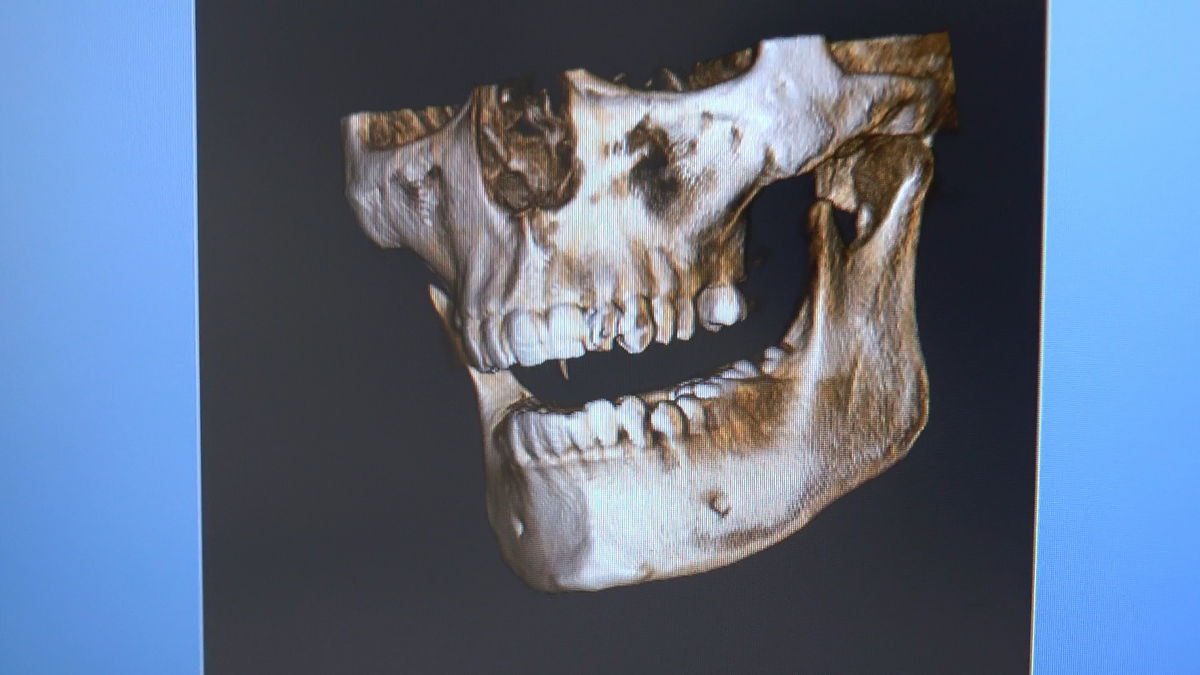

Practiculum Implantologii – Sezon VI, sesja 3, część 1